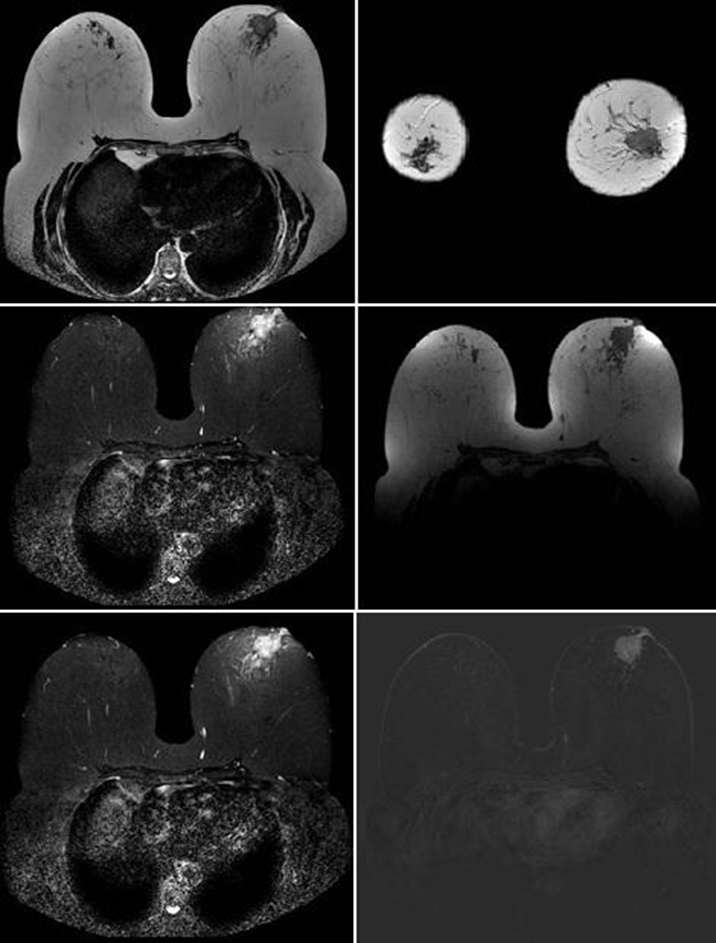

Breast Injuries Classified By Bi-Rads By Magnetic Resonance And Confirmed By Biopsy

Gustavo Vieira Soares De Carvalho, João Italo Fortaleza de Melo, Luiz Dias Dutra, Raphael Oliveira Ramos Franco Netto, Victor Augusto Ramos Fernandes, Rebecca Corrêa Manfredini, Kayque Wellek Delgado do Amaral, Messias Villa Mendonça, Fabio Rocha, Juliana de Almeida Rodrigues Franco Nett, Grissom Soares de Carvalho

International Journal of Innovative Research in Medical Science·August 10, 2020